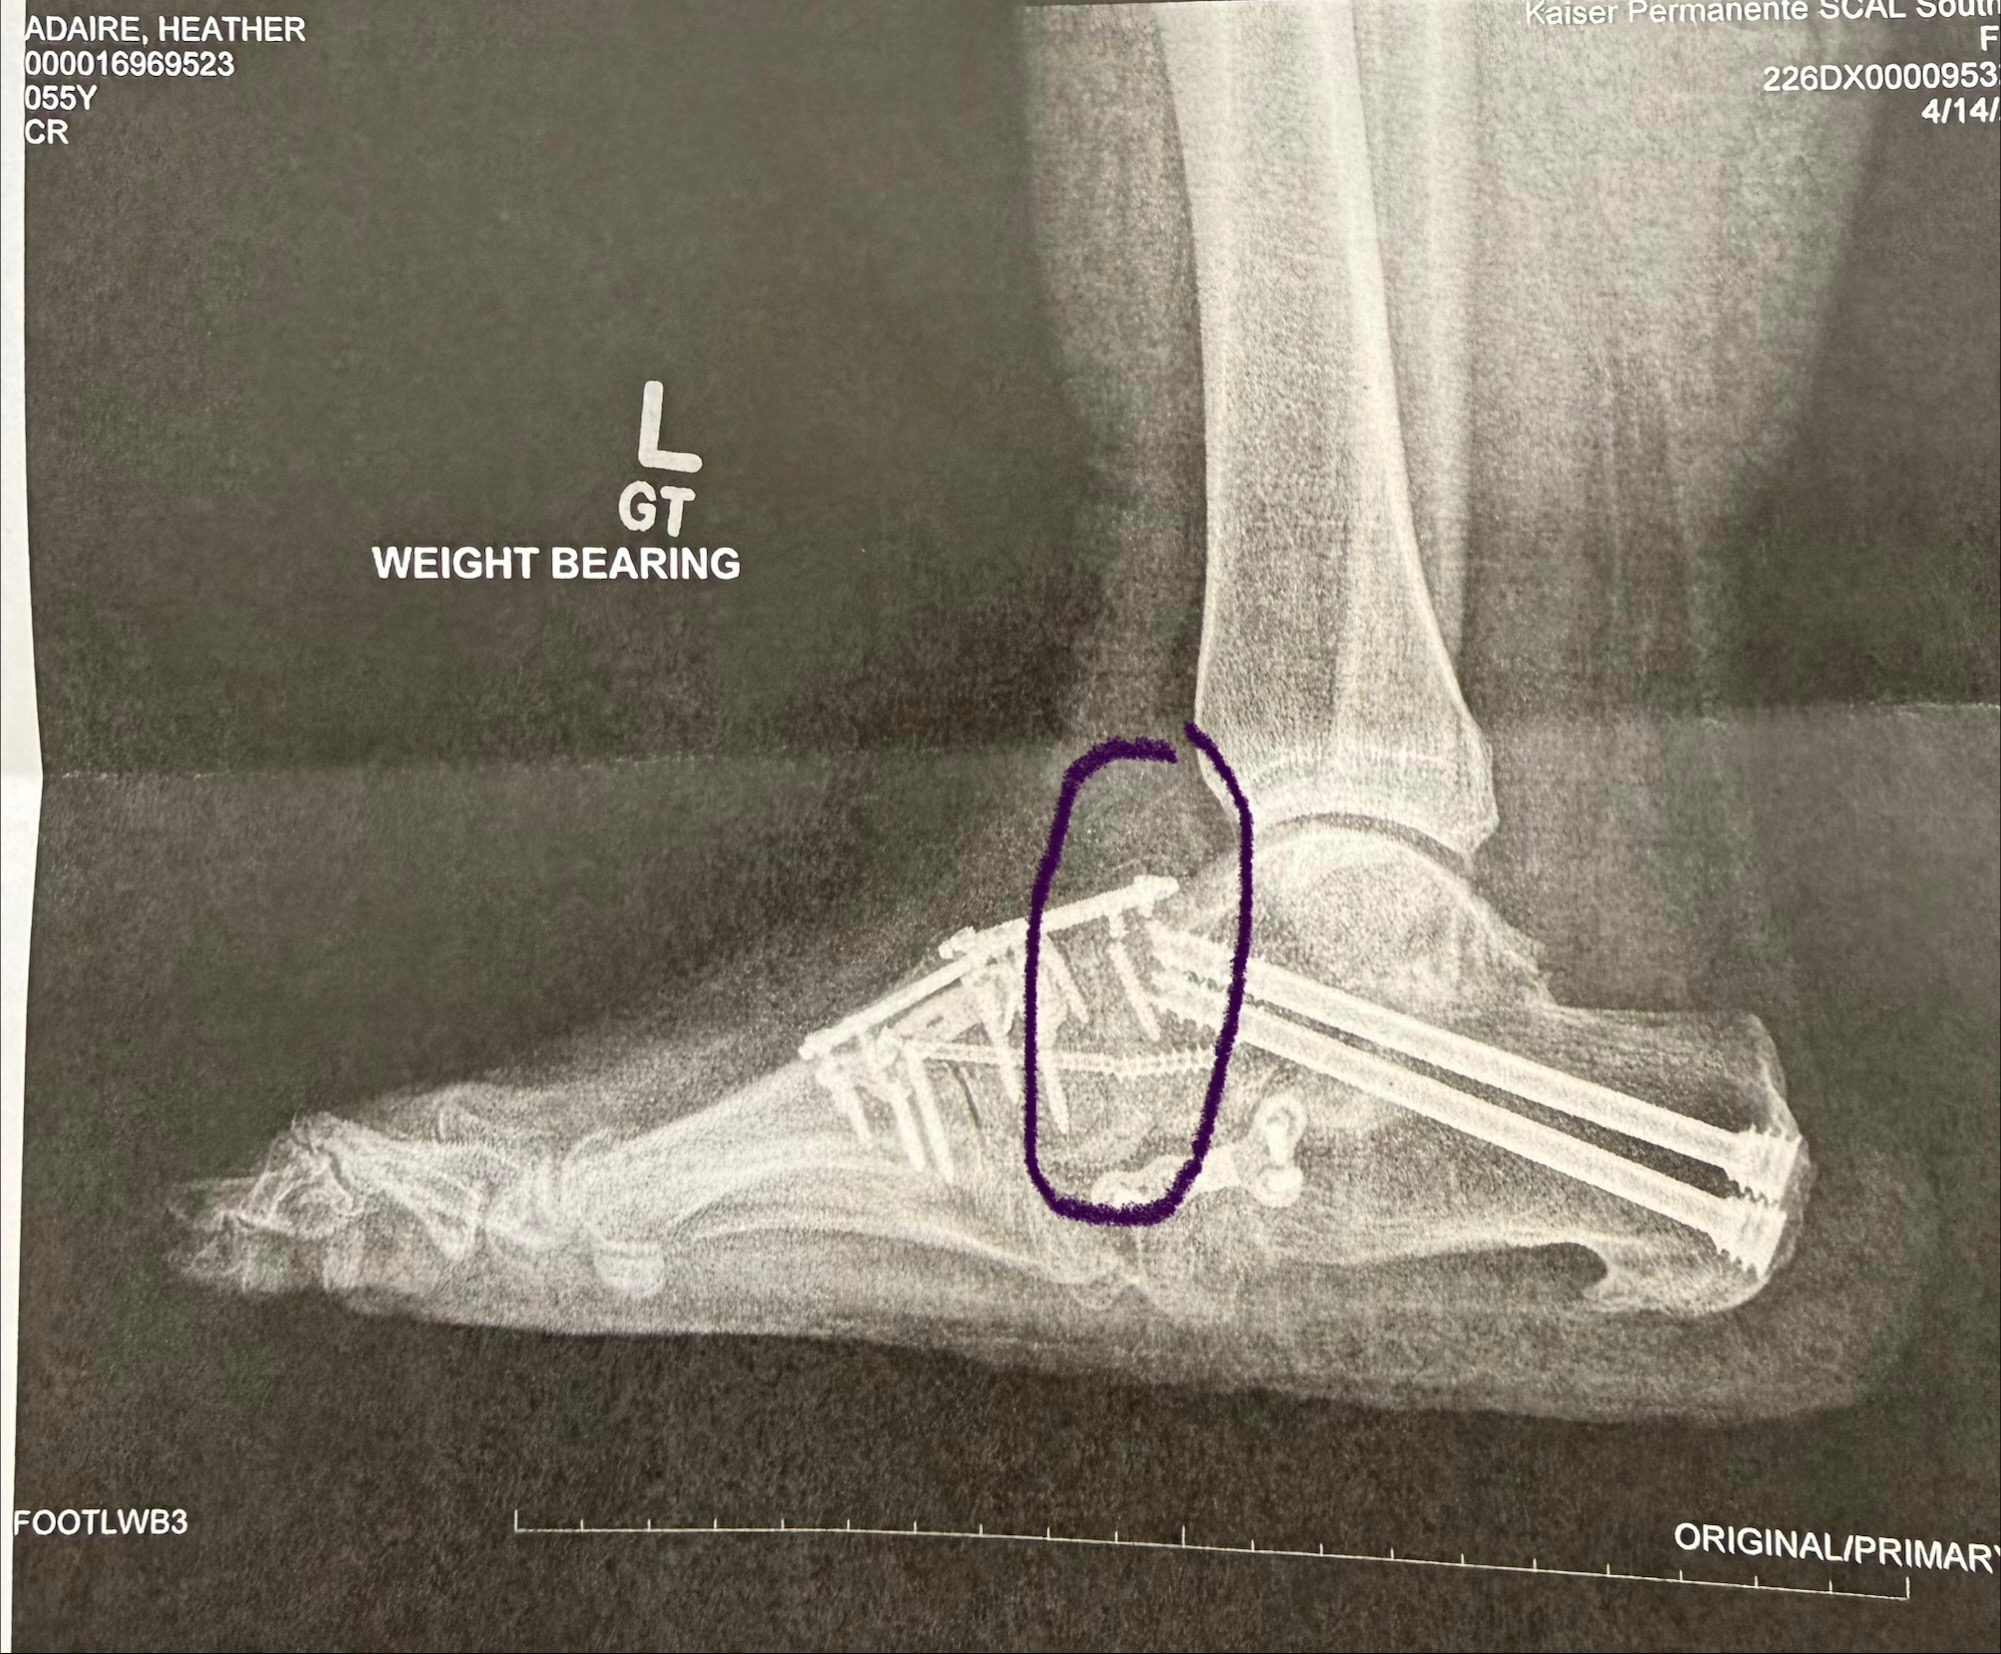

Over the past several months, I have faced a series of unexpected medical challenges. After undergoing surgery, I experienced complications that led to multiple trips to the emergency room. Just as I was hoping to recover, I learned that I need another surgery to repair broken hardware in my foot, which will take place on June 3rd. This news has been overwhelming, especially since it means I will be unable to work for at least six months while I heal.